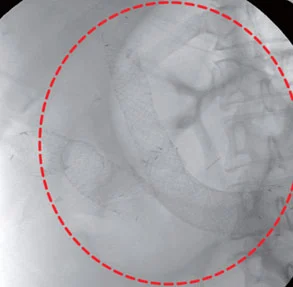

L’occlusione intestinale è una condizione patologica in cui il normale flusso del contenuto intestinale (liquidi, solidi e gas) viene bloccato. Questo può avvenire parzialmente o completamente, con conseguenti sintomi come dolore addominale, gonfiore e difficoltà nell’espulsione di feci o gas.

Definita anche ileo, dal greco eilein (che significa “serrare” o “torcere”), questa condizione può avere diverse cause. Può essere provocata da un ostacolo meccanico, come ad esempio un’ernia, un tumore o le aderenze post-chirurgiche, che impediscono il normale passaggio del contenuto intestinale. In altri casi, l’occlusione può essere causata da un strangolamento intestinale, che compromette il flusso sanguigno e porta a una condizione di ischemia (mancanza di ossigeno ai tessuti intestinali), che richiede un trattamento urgente.

Esiste anche un tipo di occlusione chiamata ileo paralitico, in cui la peristalsi (il movimento naturale dell’intestino) si arresta. Questo può accadere per vari motivi, come traumi addominali, infezioni, peritoniti, complicazioni post-operatorie, o l’assunzione di alcuni farmaci, come gli oppiacei, che rallentano il funzionamento intestinale.